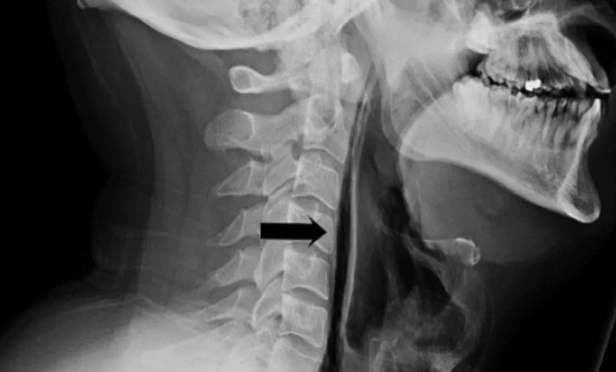

34-Π»Π΅Ρ‚Π½ΠΈΠΉ ΠΆΠΈΡ‚Π΅Π»ΡŒ ΠšΠ°Ρ€Π΅Π»ΠΈΠΈ ΠΏΠΎΠ»ΡƒΡ‡ΠΈΠ» ΡΠ΅Ρ€ΡŒΡ‘Π·Π½ΡƒΡŽ Ρ‚Ρ€Π°Π²ΠΌΡƒ, Π·Π°ΠΆΠ°Π² нос Π²ΠΎ врСмя чихания. Π­Ρ‚ΠΎ ΠΏΡ€ΠΈΠ²Π΅Π»ΠΎ ΠΊ Ρ€Π°Π·Ρ€Ρ‹Π²Ρƒ ΠΏΠΈΡ‰Π΅Π²ΠΎΠ΄Π° β€” Π²ΠΎΠ·Π΄ΡƒΡ… ΠΏΠΎΠΏΠ°Π» Π² Ρ‚ΠΊΠ°Π½ΠΈ шСи, Π²Ρ‹Π·Π²Π°Π² ΠΎΡ‚Ρ‘ΠΊ ΠΈ ΡΠΈΠ»ΡŒΠ½ΡƒΡŽ боль, сообщаСт Β«Daily ΠšΠ°Ρ€Π΅Π»ΠΈΡΒ».

Π’Ρ€Π°Ρ‡ΠΈ ΠΏΡ€Π΅Π΄ΡƒΠΏΡ€Π΅ΠΆΠ΄Π°ΡŽΡ‚: ΠΏΠΎΠΏΡ‹Ρ‚ΠΊΠΈ ΠΏΠΎΠ΄Π°Π²ΠΈΡ‚ΡŒ Ρ‡ΠΈΡ…Π°Π½ΠΈΠ΅ ΠΌΠΎΠ³ΡƒΡ‚ нанСсти Π²Ρ€Π΅Π΄ ΠΎΡ€Π³Π°Π½ΠΈΠ·ΠΌΡƒ, Ρ‚Π°ΠΊ ΠΊΠ°ΠΊ ΡΠΎΠ·Π΄Π°ΡŽΡ‚ ΠΈΠ·Π±Ρ‹Ρ‚ΠΎΡ‡Π½ΠΎΠ΅ Π΄Π°Π²Π»Π΅Π½ΠΈΠ΅.